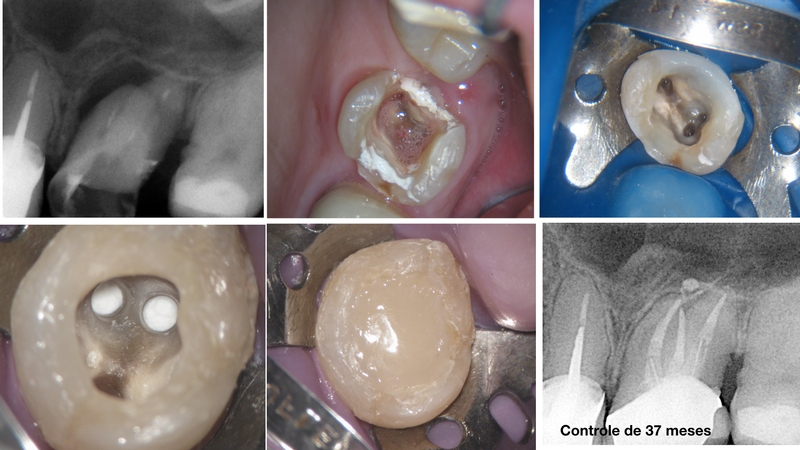

Segue sequência de casos em que os dentes, inicialmente foram encaminhados para implantes. Querendo uma segunda opinião, orientei no sentido de tentarmos, de f0rma conscîente, uma abordagem apropriada, seguindo um protocolo criterioso. As respostas foram surpreendentes…

• Rettratamento de canal atípico